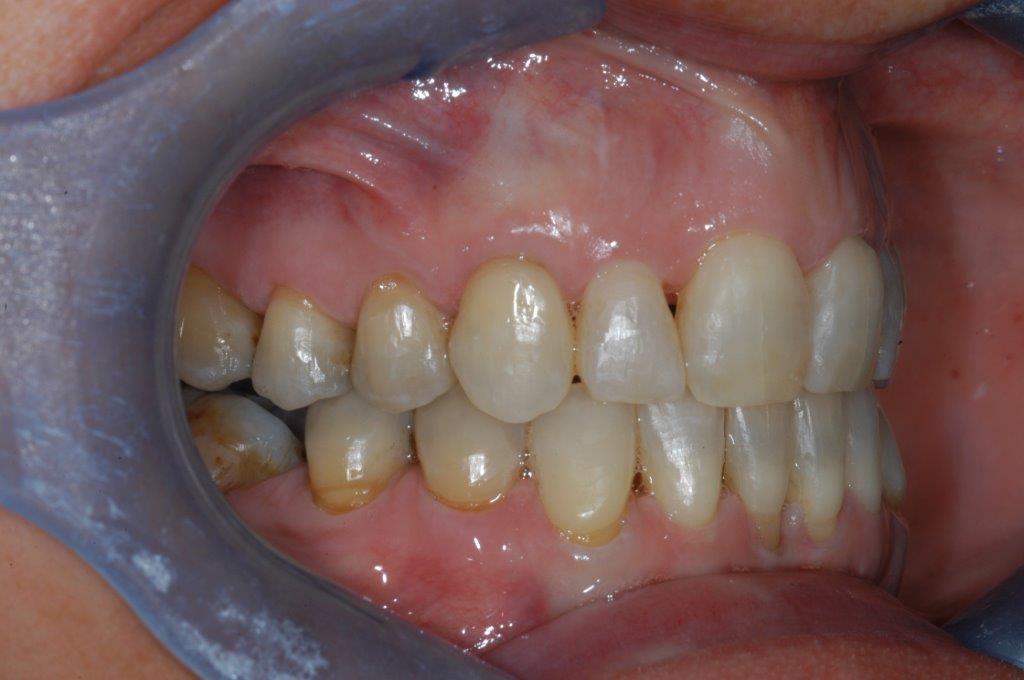

This mouth had recession on just one tooth with very little bone to support the tooth. The area needed support and thickness. The tissue was placed and the area now has thicker tissue to withstand the forces that the patient needs to place on it.